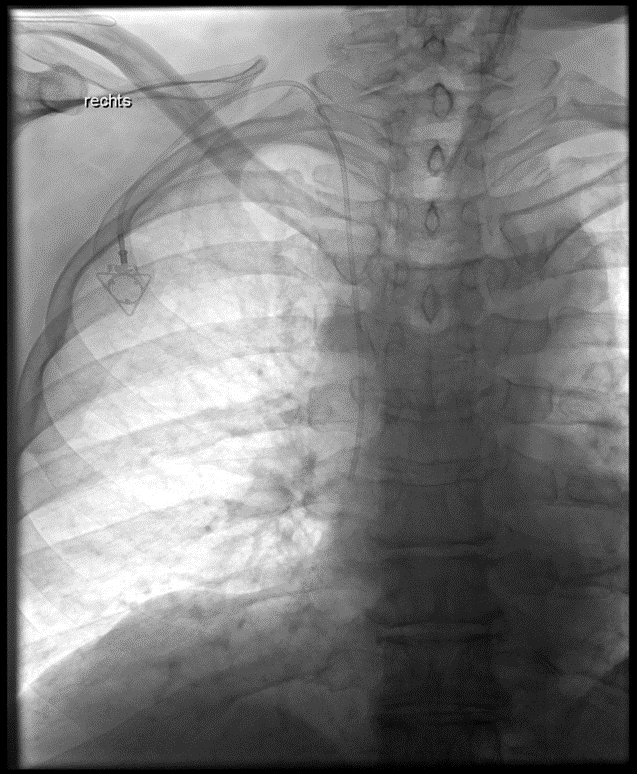

Implantation eines Port-Systems über die rechte innere Drosselvene (V. jugularis interna dextra)

(Bild 1 von 4)